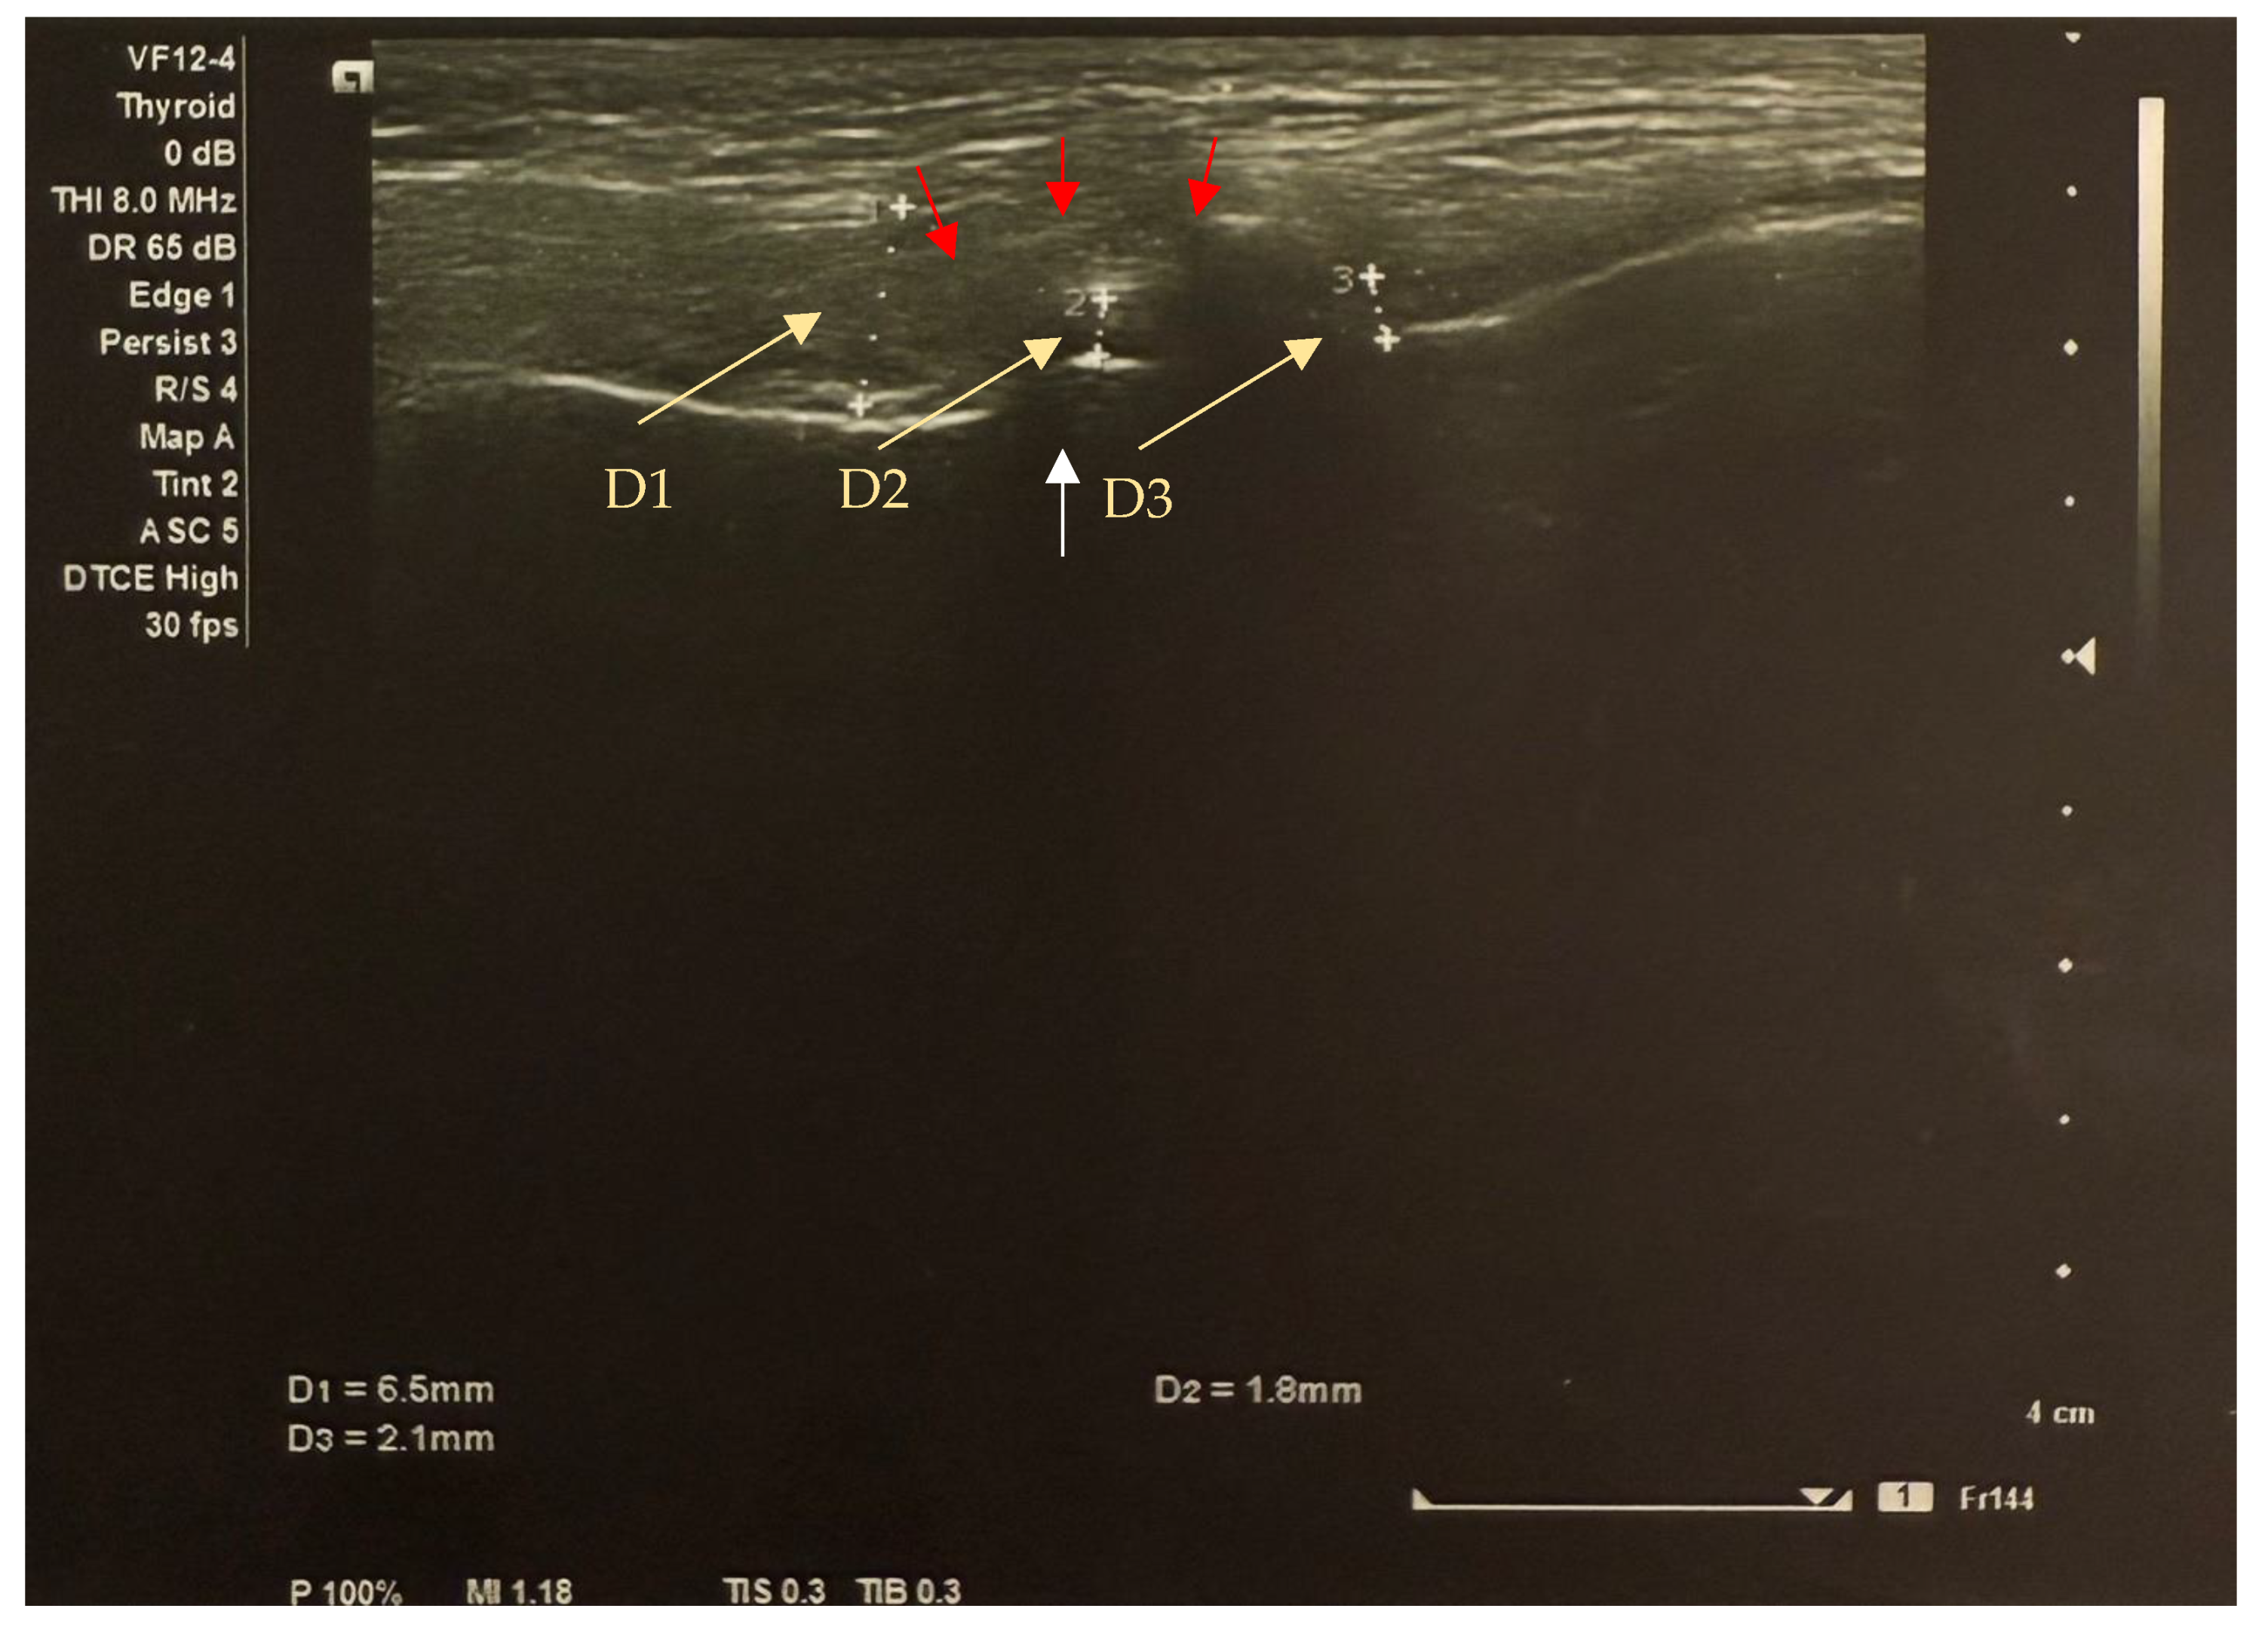

- Manfredini, D.; Guarda-Nardini, L. Ultrasonography of the temporomandibular joint: A literature review. Int. J. Oral Maxillofac. Surg. 2009, 38, 1229–1236. [Google Scholar] [CrossRef]

- Habibi, H.A.; Bayramoglu, Z.; Caliskan, E.; Ozturk, M. Ultrasound evaluation of the temporomandibular joint in healthy children and adolescents. Acta Medica Alanya 2021, 5, 175–180. [Google Scholar] [CrossRef]

- Wojciechowska, B.; Szarmach, A.; Michcik, A.; Sikora, M.; Drogoszewska, B. Is Ultrasonography an Effective Method for Diagnosing Degenerative Changes in the Temporomandibular Joint? Biomedicines 2024, 12, 2915. [Google Scholar] [CrossRef] [PubMed]

- Kim, J.H.; Park, J.H.; Kim, J.W.; Kim, S.J. Can ultrasonography be used to assess capsular distention in the painful temporomandibular joint? BMC Oral Health 2021, 21, 497. [Google Scholar] [CrossRef]

- LK, S.K.; Zachariah, G.P.; Chandran, S. Ultrasonography: A step forward in temporomandibular joint imaging. A preliminary descriptive study. Clin. Pract. 2019, 9, 1134. [Google Scholar] [CrossRef]

- Tonni, I.; Borghesi, A.; Tonesi, S.; Fossati, G.; Ricci, F.; Visconti, L. An ultrasound protocol for temporomandibular joint in juvenile idiopathic arthritis: A pilot study. Dentomaxillofac. Radiol. 2021, 50, 20200399. [Google Scholar] [CrossRef] [PubMed]

- Kirkhus, E.; Gunderson, R.B.; Smith, H.J.; Flatø, B.; Hetlevik, S.O.; Larheim, T.A.; Arvidsson, L.Z. Temporomandibular joint involvement in childhood arthritis: Comparison of ultrasonography-assessed capsular width and MRI-assessed synovitis. Dentomaxillofac. Radiol. 2016, 45, 20160195. [Google Scholar] [CrossRef] [PubMed]

- Talmaceanu, D.; Lenghel, L.M.; Bolog, N.; Buduru, S.; Leucuta, D.; Rotar, H. High-resolution ultrasound imaging compared to magnetic resonance imaging for temporomandibular joint disorders: An in vivo study. Eur. J. Radiol. 2020, 132, 109291. [Google Scholar] [CrossRef] [PubMed]